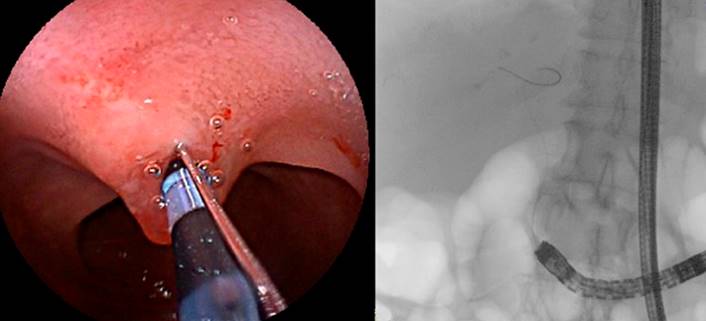

Se ingresa por el asa biliopancreática (con ayuda de la fluoroscopia) hasta el muñón duodenal (aproximadamente 150 centímetros de longitud) (Figura 3). Se identifica la papila duodenal de aspecto normal (en el cuadrante superior) (Figura 4). Se intenta la canulación con catéter punta cónica, con papilótomo de arco y con papilótomo de aguja, pero no es posible avanzar la guía hacia la vía biliar, por lo que se utiliza un papilótomo invertido; se logra avanzar la guía hidrofílica hacia la vía biliar (Figura 5).

Figura 3 Muñón duodenal mediante visión endoscópica y fluoroscópica. Fuente: archivo de los autores.

Figura 5 Canulación con papilótomo invertido y avance de la guía hacia la vía biliar. Fuente: archivo de los autores.